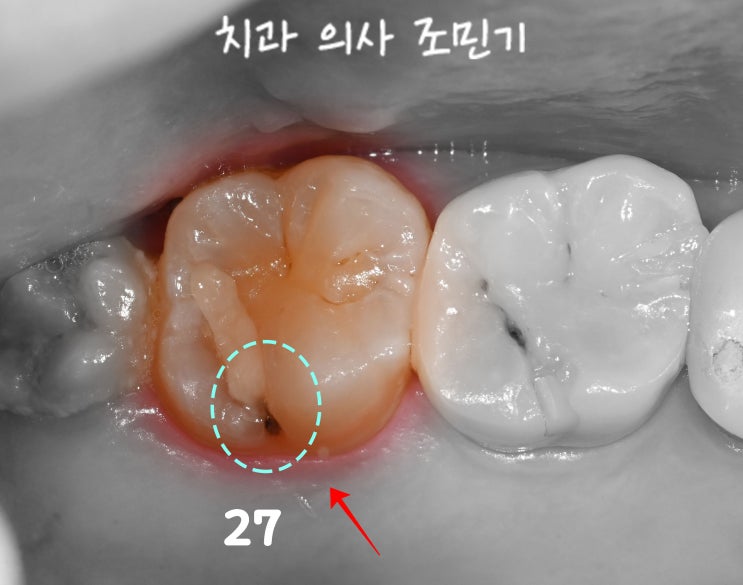

신촌 치과 : 어금니 수복물 하방으로 생긴 충치 , 이차우식 치아 emax 인레이 재치료

안녕하세요. 신촌 치과 의사 조민기입니다. 기존에 치료 받은 곳이더라도 시간이 흐르면서 여러 문제가 일...